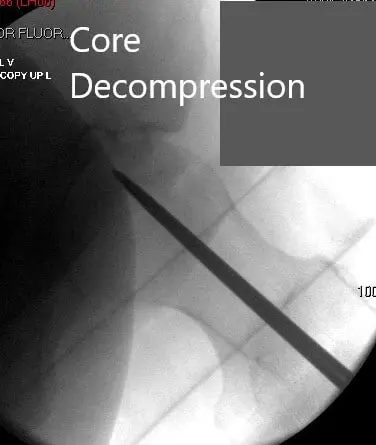

Jamshidi needle was inserted into the left iliac crest and about 180 ml of fluid was aspirated. The aspirate was processed using the harvest system. The two guidewires were then placed into the left hip under fluoroscopic control in a percutaneous manner. Core decompression was performed at the location of the avascular necrosis.

Core Decompression at the site of avascular necrosis.